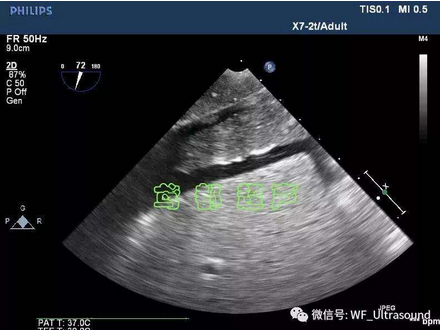

影像学检查不仅有助于IVL的早期诊断,还可为手术治疗提供充分的资料,对确定手术的范围及实施方案具有指导意义。...

静脉内平滑肌瘤病(intravenous leiomyomato-sis,IVL)是起源于子宫的一种特殊类型的良性平滑肌肿瘤....

静脉内平滑肌瘤极罕见,多见于45岁左右妇女。临床表现为不规则出血,腹部不适,盆腔包块;瘤栓可见于下腔静脉、肺内等。...